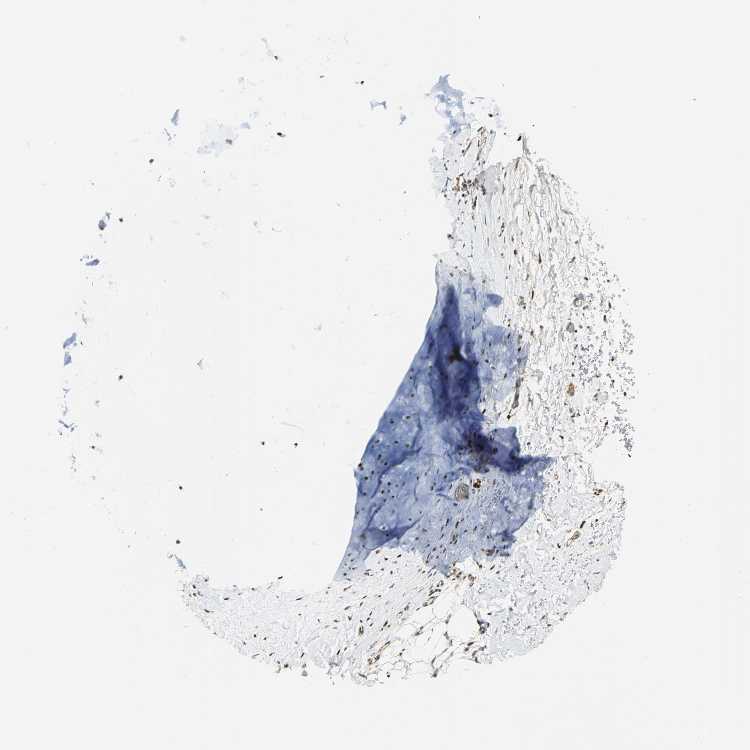

SOFT TISSUE 1 - Antibody stainingi

Antibody staining in the annotated cell types in the current human tissue is reported as not detected, low, medium, or high, based on conventional immunohistochemistry profiling in selected tissues. This score is based on the combination of the staining intensity and fraction of stained cells.

Each image is clickable and will lead to virtual microscopy that enables deeper exploration of all samples and also displays staining intensity scores, fraction scores and subcellular localization as well as patient and tissue information for each sample.

Antibody HPA004892

Fibroblasts Medium

Peripheral nerve Not detected